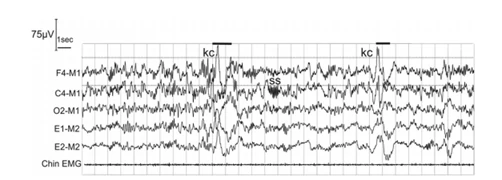

K复合波(K-Complex)

K复合波是持续时间大于0.5s的双向波,通常是一个正波后接着一个负波(或者是一个负波后接着一个正波)。常出现于额区。

Stage N2

A. 出现一个或者多个与觉醒无关的K复合波

B. 出现1个或者多个睡眠纺锤波